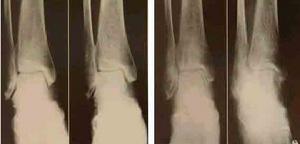

X線表現,單純滑膜結核可見骨質疏鬆及關節囊腫脹。在踝關節的側位片上,正常脂肪透亮區被推開、壓縮變窄或消失;關節內積液多時,可見關節間隙增寬。

單純骨結核可見局部有溶骨性破壞,磨砂玻璃樣改變或死骨形成。

由單純滑膜轉變為全關節結核時,可見軟骨下骨板模糊或邊緣骨質破壞,晚期關節破壞嚴重,出現畸形或強直。

1.X線檢查 單純性滑膜結核在X線片上表現為骨質疏鬆與軟組織腫脹陰影 單純性骨結核則表現為囊性溶骨性改變或毛玻璃樣改變,其間死骨並不多見。發展至全關節結核時則表現為進行性關節間隙變窄及不對稱,並可看到邊緣性骨破壞。隨著病變發展,骨破壞加劇,軟骨下骨皮質消失,至後期,踝關節毀損明顯,但極少發生骨性強直。除非有繼發感染存在,一般不會出現骨硬化表現。